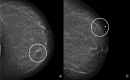

Radial scar (RS) or complex sclerosing lesions (CSL) if > 10 mm is a benign lesion with an increasing incidence of diagnosis (ranging from 0.6 to 3.7%) and represents a challenge both for radiologists and for pathologists. The digital mammography and digital breast tomosynthesis appearances of RS are well documented, according to the literature. On ultrasound, variable aspects can be detected. Magnetic resonance imaging contribution to differential diagnosis with carcinoma is growing. As for the management, a vacuum-assisted biopsy (VAB) with large core is recommended after a percutaneous diagnosis of RS due to potential sampling error. According to the recent International Consensus Conference, a RS/CSL lesion, which is visible on imaging, should undergo therapeutic excision with VAB. Thereafter, surveillance is justified. The aim of this review is to provide a practical guide for the recognition of RS on imaging, illustrating radiological findings according to the most recent literature, and to delineate the management strategies that follow.